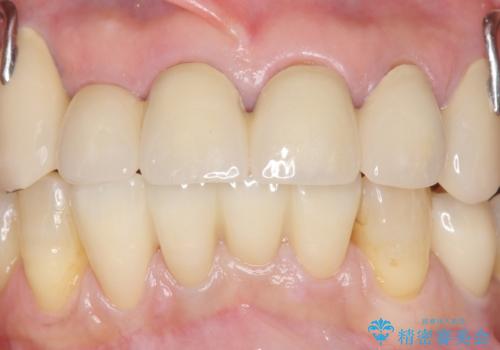

自然な仕上がりに喜んで下さいました。

クラウンを連結することにより気にされていた動揺もなくなり、安心して頂けました。

被せ物の種類:オールセラミッククラウン スタンダード